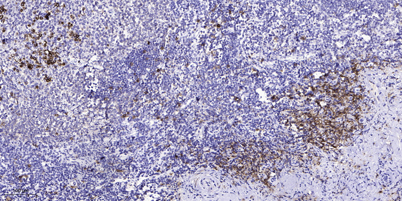

IF

IHC

Recomended Dilution WB 1:500-2000 ,Immunohistochemistry: 1/100 - 1/300. ELISA: 1/5000. Not yet tested in other applications.